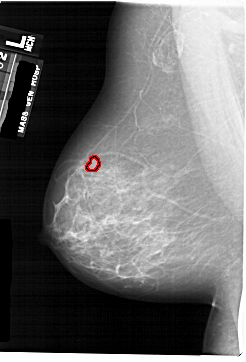

FILE: A_1742_1.LEFT_MLO.OVERLAY TOTAL_ABNORMALITIES 1 ABNORMALITY 1 LESION_TYPE MASS SHAPE LOBULATED MARGINS CIRCUMSCRIBED ASSESSMENT 4 SUBTLETY 2 PATHOLOGY BENIGN TOTAL_OUTLINES 1 BOUNDARY |

FILE: A_1742_1.LEFT_CC.OVERLAY TOTAL_ABNORMALITIES 1 ABNORMALITY 1 LESION_TYPE MASS SHAPE LOBULATED MARGINS CIRCUMSCRIBED ASSESSMENT 4 SUBTLETY 2 PATHOLOGY BENIGN TOTAL_OUTLINES 1 BOUNDARY |